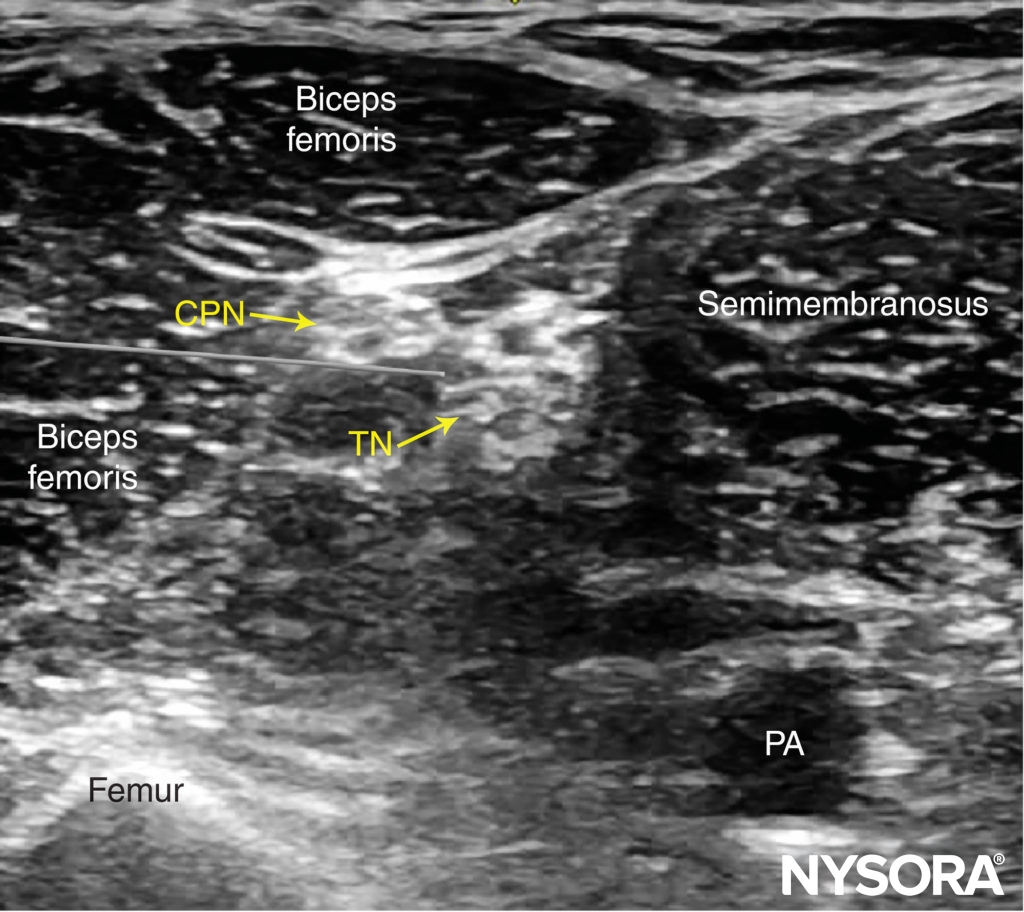

Beginning with the transducer in the transverse position at the popliteal crease, the popliteal artery is identified, aided with color Doppler US when necessary, at a depth of approximately 3–4 cm. The popliteal vein accompanies the artery at it is positioned just superficial (posterior) to it. On either side of the artery are the biceps femoris muscles (laterally) and the semimembranosus and semitendinosus muscles (medially). The tibial nerve is positioned superficial and lateral to the vein and is seen as a hyperechoic, oval or round structure with a honeycomb pattern (Figure 3). Asking the patient to dorsiflex and plantar flex the ankle makes the two sciatic nerve branches twist or move in relation to each other. Usually, tilting the transducer caudally is necessary to bring out the nerve from the neighboring adipose tissue.

FIGURE 3. Sonoanatomy of the sciatic nerve at the popliteal fossa. The two main divisions of the sciatic nerve, the tibial nerve (TN) and the common peroneal nerve (CPN), are seen immediately lateral and superficial to the popliteal vein (PV) and artery (PA). This image was taken at 5 cm above the popliteal fossa crease, where the TN and CPN have just started diverging.

Once the tibial nerve has been identified, the CPN is visualized slightly more superficial and lateral to the tibial nerve. The transducer should be slid proximally until the tibial and peroneal nerves are visualized coming together to form the sciatic nerve before its division (Figure 4). This junction usually occurs at a distance 5–10 cm from the popliteal crease but may occur very close to the crease or, less commonly, more proximally in the thigh.